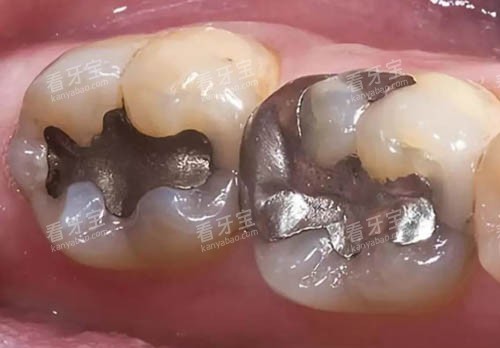

补牙的核心是“填补牙齿缺损”,价格差异主要取决于材料和缺损程度。

适用于浅龋或小面积缺损,常用材料是玻璃材料和光固化复合树脂。

玻璃材料价格亲民,约200元/颗,但耐磨性较差,适合后牙咬合面不频繁接触的区域;光固化复合树脂性能更优,价格约500元/颗,颜色接近天然牙,耐磨性强,是前牙修复的首要选择。

进口材料补牙:800-1200元起/颗

若追求更持久的结果,可选择进口生物材料,如纳米树脂或瓷化树脂。

这类材料硬度高、耐磨性强,且颜色更自然,适合前牙或对美观要求高的患者。